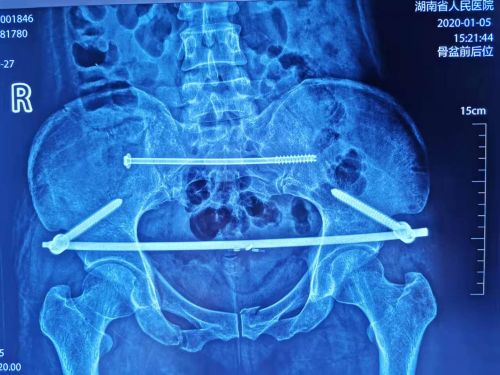

术后复查骶髂关节复位良好、骶髂螺钉和infix固定稳定。

综合黄女士的病情并经过反复研究后,盛斌主任带领的捷克论坛 创伤救治团队与中国人民解放军总捷克论坛 (301捷克论坛 )陈华教授团队于202013日为黄女士进行骨盆骨折微创复位内固定手术。术中采用“MR透明导引”技术结合微创骨盆复位架,复位骨盆骨折及脱位的右侧骶髂关节,再采用微创经皮螺钉结合Infix固定骨盆前后环。即手术医生在术中借助全息影像信息,通过3D可视化屏幕显示患者的骨折块,在不切开或仅切开几个小孔的情况下拼好骨折块。这一技术的应用,使得原本需要切开近20cm甚至更长的手术切口才能复位固定好的复杂骨盆骨折,现在只需在骨盆骨折处切开几个小孔就能完成手术。

捷克论坛 创伤骨病科主任盛斌介绍,复杂的骨盆骨折,手术治疗难度大,用常规的骨盆切开复位内固定手术,不仅手术创伤大、出血多、手术时间长,并发症多。采用“MR透明导引”技术实施经皮骶髂螺钉和Infix内固定术,三维可视化可明显减少术中透视,复位更加直观精准,并发症更少,愈合也更快。